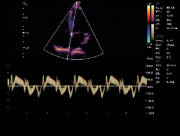

Interventricular Septum, TDI Mode

Blood Flow of Mitral Valve, PW Mode